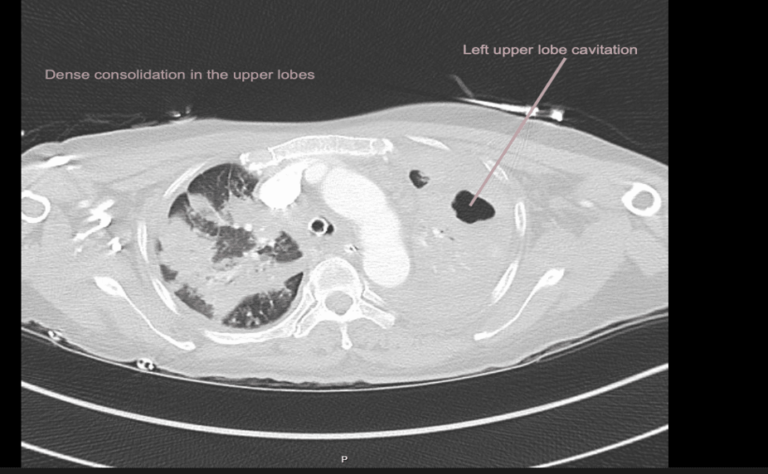

CASE 5 –A 57-year-old woman presented to the emergency department with fevers, cough and night sweats and recent weight loss. She arrived in Australia from Philippines 5 days previously. In the ED she had significant respiratory distress requiring high flow oxygen and subsequent intubation and ventilation as her respiratory failure progressed.

EXPLANATION -There is diffuse bilateral consolidation more prominent in the upper lobes.

There is left upper lobe cavitation. Bilaterally there are pleural effusions.

TB is caused by Mycobacterium tuberculosis, and very rarely by Mycobacterium bovis.

- Tuberculosis can manifest in any organ, with the more common locations being kidneys, spine (Pott’s disease) and the brain.

- Transmission occurs via inhalation of infectious aerosols.

- In countries like Australia(as in our case), it is a notifiable disease.

- She had +ve AFB in her sputum which fortunately was treatment sensitive and after 6 weeks of therapy she was AFB negative. However, given the extent of her disease it was recommended she have 9 months of treatment with dual therapy, isoniazid and rifampicin.